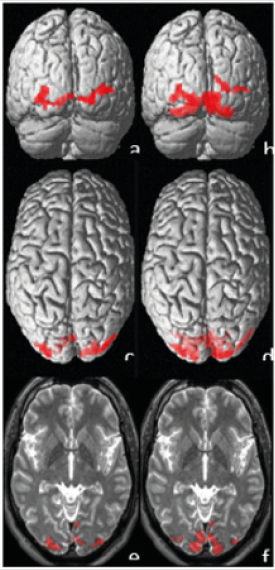

As the bionic eye is most commonly indicated in the patients with RP we will focus mainly on this diagnostic group. A prerequisite for the effectiveness of this system is a preservation of integrity of the middle and inner retinal structures, the visual pathway and the subcortical and cortical brain centers [7]. RP is a disease that primarily affects rods and cones and underlying retinal pigment epithelium. The inner core and plexiform layer, ganglion cells and their fibers undergo degeneration and are replaced by gliotic tissue. These changes are variable and can be visible at a later stage of the disease [8]. Our long experience in electrophysiology of vision show that already at the early phases of the diseases the rods but also the macular retinal structures including ganglion cells are altered. As a result, the optic nerve and the visual cortex are also damaged. We selected two patients with RP for this study. Both had similar subjective visual functions but a different age. The first patient was a male aged 38 years with RP within the Usher’s syndrome. VARE: 0.5 naturally, VA-LE: 0.3 naturally. However, correction did not improve the sight. The perimetric examination showed a concentric narrowing of the visual fields to ten and five degrees in the right and left, respectively. Functional magnetic resonance imaging (fMRI) showed a significant decrease of activity, more following stimulation of the left eye (Figure 1). According to our methodology, the mean values of fMRI in the healthy population (for the corresponding age group) following monocular stimulation were: 9.200±2.700 activated voxels [9]. The second patient was also a male of a higher age (63 years) with the VA-RE: 0.2, VA-LE: 0.3, naturally. However, correction did not improve the sight. The perimetric examination showed a concentric narrowing of the visual fields to ten and five degrees in the right and left, respectively. Electrophysiological examination showed a missing response bilaterally. Both in ERG, PERG and PVEP. Even with the above-mentioned visual functions, fMRI did not show any brain activity in the second patient after stimulation of each eye separately [10].

Figure 1: The activation after visual stimulation of the left (a, c, e) and right (b, d, f) eye. Upper line shows coronal 3D view (a, b), middle axial 3D view (c, d) and lower line shows selected 2D slices with activation projected over patients T2W scans. The entire number of statistically significant voxels of activation was 290 in case of left eye stimulation and 950 for right eye stimulation (threshold of p=0.05 with FWE correction was used).